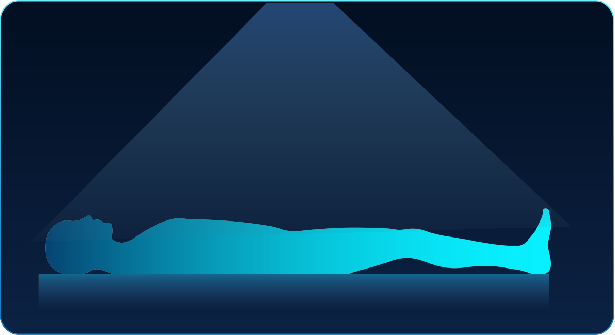

Sky-eye intelligent positioning system

Using HD camera combined with auto-positioning technology, "Sky eye" can greatlyimprove efficiency on the whole scanning workflow which realizes fully intelligentscanning and navigation functions like auto-positioning, adaptive scout fieldselecting and protocol assisting

Precision in Workflow (One-Click Workflow, Patient-Centric Care)

When a patient is mis-positioned, it may lead to

38% increase in dose*

22% increase in image noise*

Accu-Positioning

A deep learning-driven automated positioning technology based on 3D camera, which identify anatomical points through sensors, generation 3D image information and automatically locating the position.

Accu-ISO

By utilizing a 3D camera and advanced technology, the system is able to identify the exact center of the scanning area with pinpoint accuracy, aligning it with the target under just one-click.